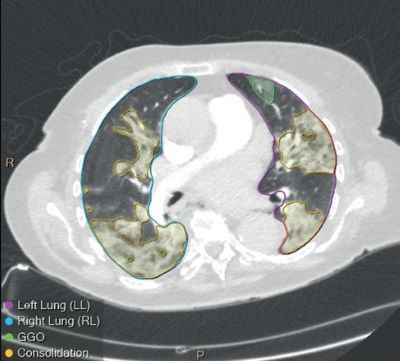

CT Pulmo Auto Results

CT Pulmo Auto Results is an AI-based automated image analysis application that identifies several radiological findings in chest CT (e.g., consolidation and ground glass opacity) to support the management of adult patients with suspected or diagnosed COVID pneumonia